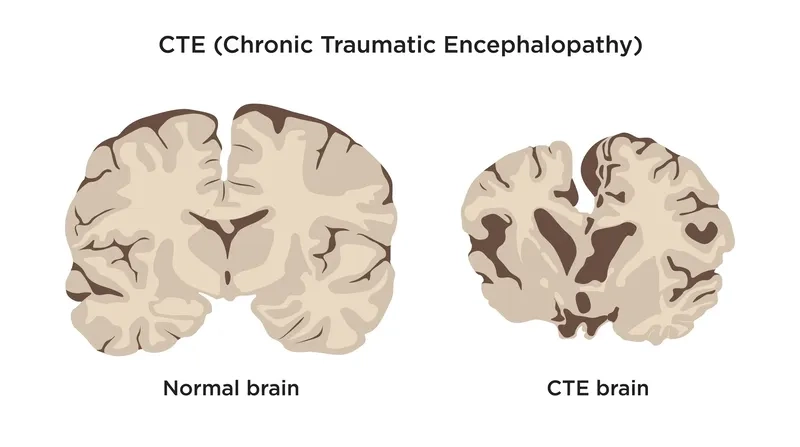

The dangers of repeated head injuries are more serious than you might think, potentially leading to Chronic Traumatic Encephalopathy (CTE). Understanding this neurodegenerative disease is crucial for athletes, veterans, and their families. Don't ignore the risks; get the facts about CTE causes and symptoms now.

- The accumulation of an abnormal protein called tau forms clumps that slowly spread throughout the brain, killing brain cells and leading to progressive decline.

Visualizing concepts related to CTE